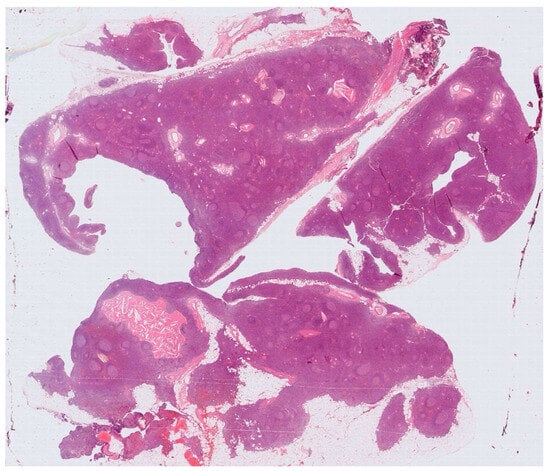

Histology showed an MTC lined by cubic epithelium and rich in lymphoid tissue, organized in germinal centers (CD10+, BCL6+, BCL2−, CD21+, CD23+), and a mantel zone (CD79A+, BCL2+), the interfollicular region represented by T-cell (CD3+), and occasional Hassall’s Corpuscles (Figure 2, Figure 3 and Figure 4).

Figure 2. A multilocular cyst with a wall composed of lymphoid tissue organized in follicular structures.